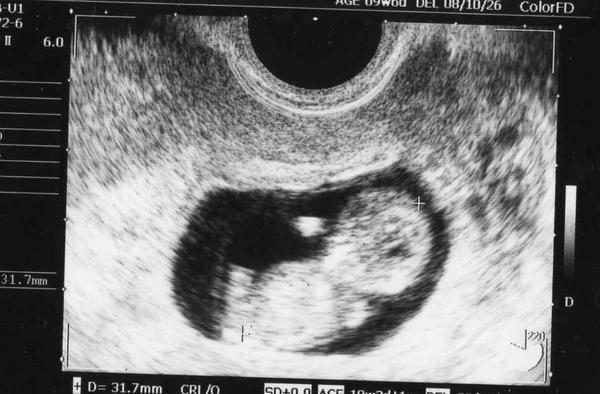

10月我要當媽媽,少爺要當爸爸了!

*目前進入第10週,預產期是10/26的天蠍寶寶

上週產檢的照片,已經看得到一個小小人形了…

31.2mm 食玩贈品大小(≧∇≦)